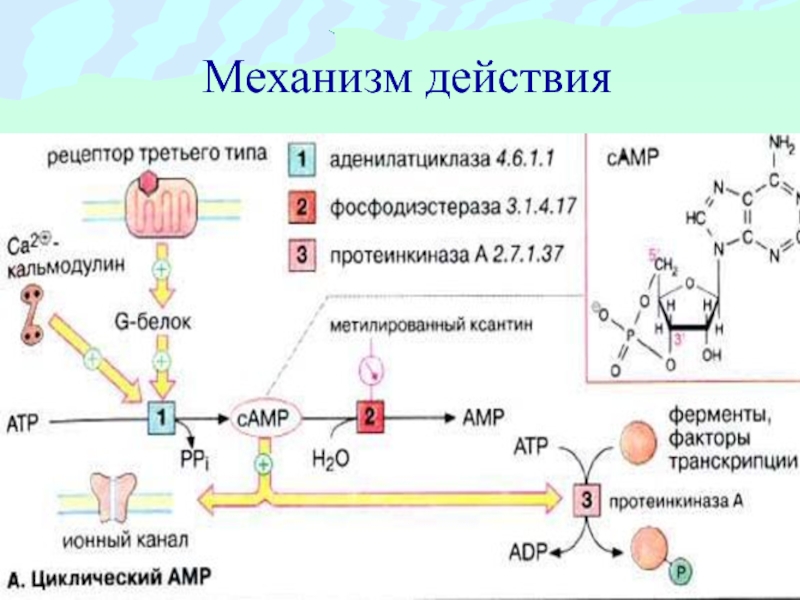

Механизмы действия антимикотиков: схемы и изображения